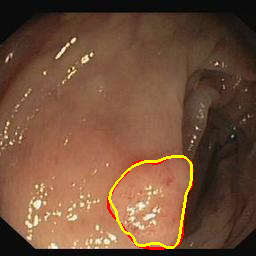

Medical image segmentation is a primary task in many applications, and the accuracy of the segmentation is a necessity. Recently, many deep learning networks derived from U-Net have been extensively used and have achieved notable results. To further improve and refine the performance of U-Net, parallel decoders along with mask prediction decoder have been carried out and have shown significant improvement with additional advantages. In our work, we utilize the advantages of using a combination of contour and distance map as regularizers. In turn, we propose a novel architecture Psi-Net with a single encoder and three parallel decoders, one decoder to learn the mask and other two to learn the auxiliary tasks of contour detection and distance map estimation. The learning of these auxiliary tasks helps in capturing the shape and boundary. We also propose a new joint loss function for the proposed architecture. The loss function consists of a weighted combination of Negative likelihood and Mean Square Error loss. We have used two publicly available datasets: 1) Origa dataset for the task of optic cup and disc segmentation and 2) Endovis segment dataset for the task of polyp segmentation to evaluate our model. We have conducted extensive experiments using our network to show our model gives better results in terms of segmentation, boundary and shape metrics.